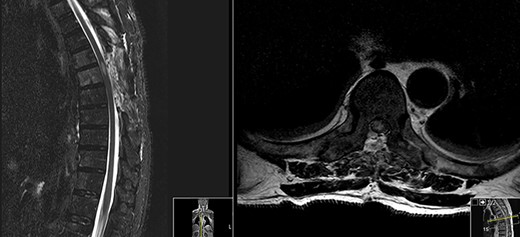

MRI done at this time showed a reduction in the T2 hyperintensity seen in both previous post-op MR scans (Fig. 3).